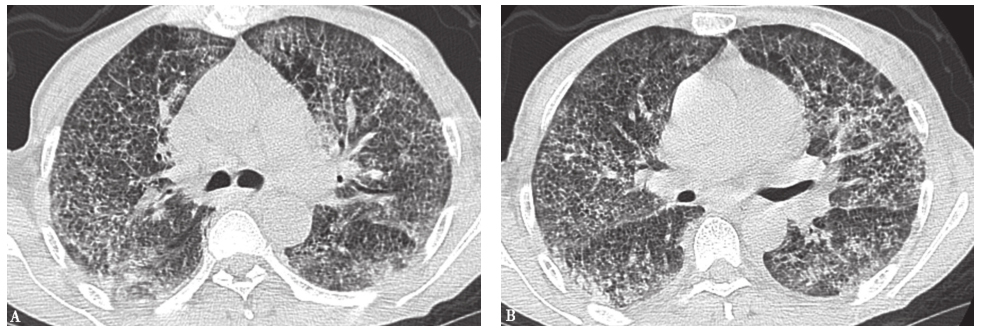

矽肺:是最常见的尘肺类型,是由于反复吸入微小的游离二氧化硅晶体颗粒导致的以肺部弥漫性纤维化为主的疾病。胸部影像学表现可见弥漫性微结节影的有急性矽肺和单纯型矽肺。急性矽肺可发生于在高浓度、高分散度二氧化硅粉尘环境中作业者,可在数月到3年内发病。胸部CT显示双肺弥漫性小叶中央性微结节影,片状磨玻璃影、小叶间隔增厚和少许实变影,可见铺路石征(图12)。单纯型矽肺胸部CT可见双肺多发微结节影,边界清晰,以上肺分布为主,部分钙化,结节多在小叶中央、间隔周围和胸膜下分布,呈淋巴管周围分布,肺门和纵隔淋巴结可以增大,可形成典型的蛋壳样钙化。

图12急性矽肺胸部影像学表现

女性患者,59岁,诊断为急性矽肺。胸部影像学表现为双肺弥漫性小叶中央性微结节,磨玻璃影、小叶间隔增厚,可见铺路石征